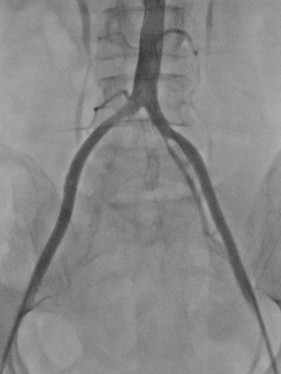

術(shù)中DSA:雙髂動(dòng)脈血流恢復(fù)